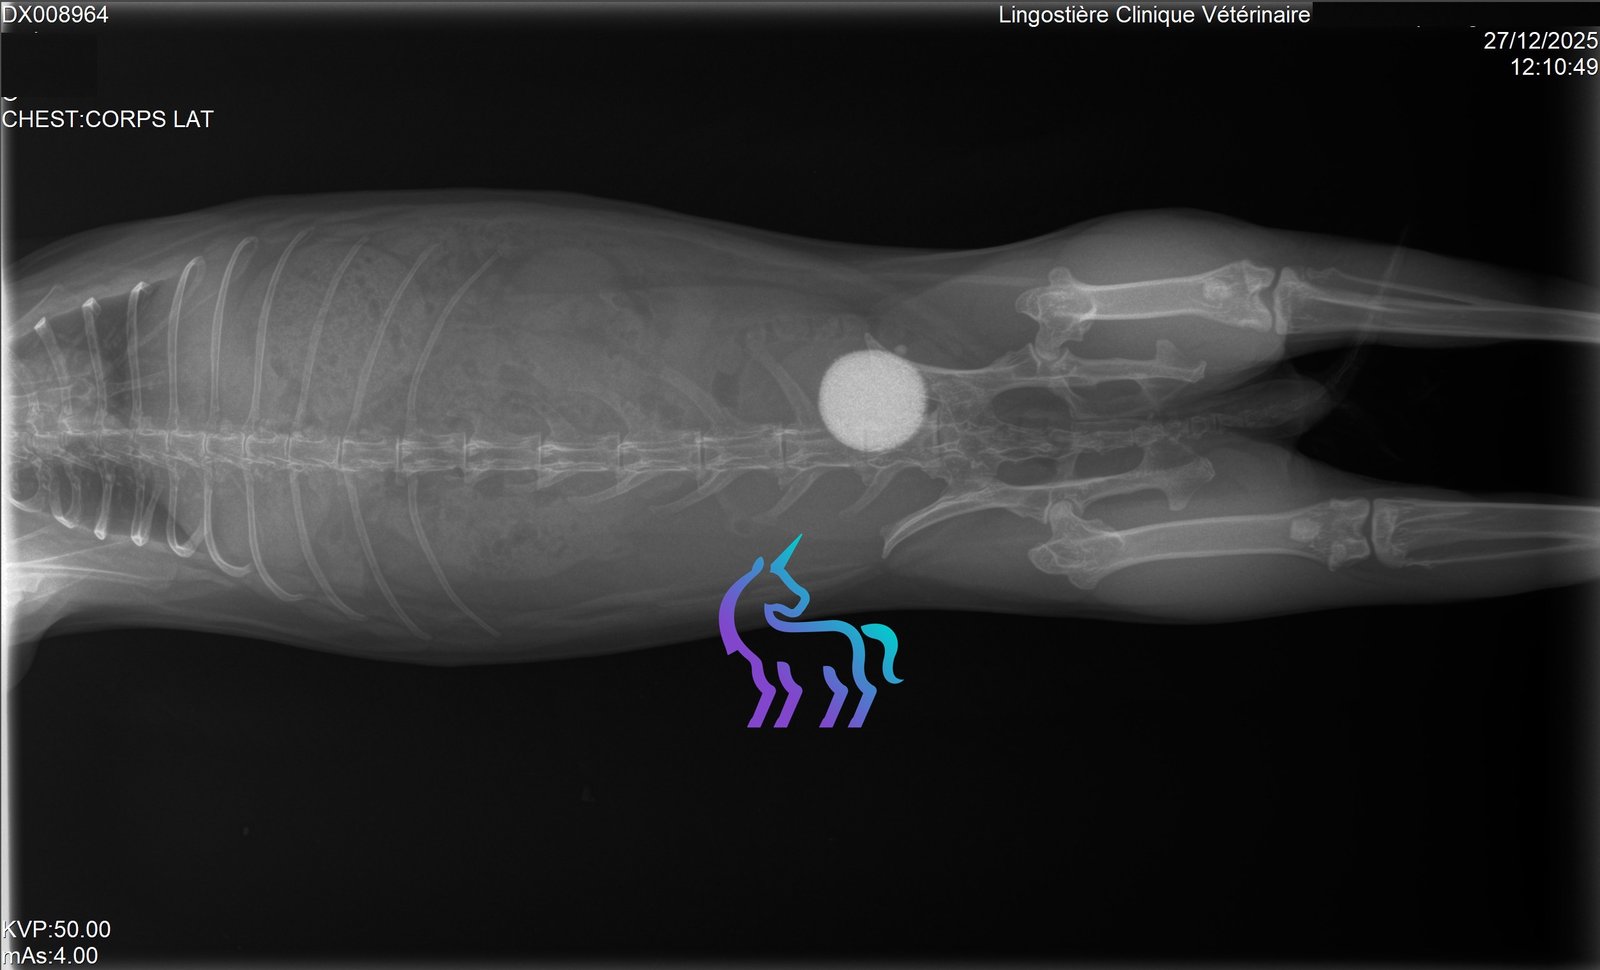

Quels examens sont utiles ?

Radiographies pour fractures/arthrose, scanner/IRM si suspicion lésion vertébrale.Amputation : dans quels cas ?

Radiographies (poumons), prélèvements bactériologiques ou scanner.7) Oreilles (otites) et chirurgie de l’oreille

Radiographie, échographie et analyse sanguine.Cystotomie : c’est quoi et quand ?